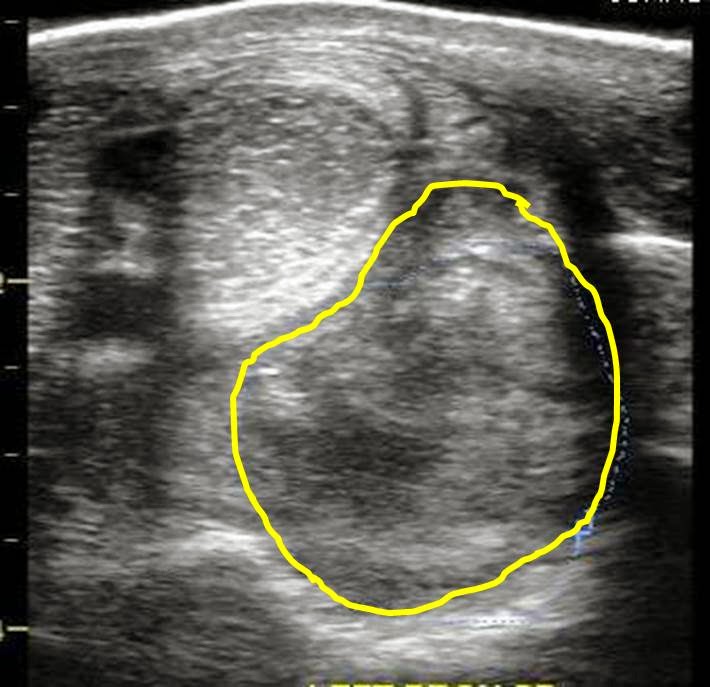

An ultrasound exam was performed to evaluate the entire suspensory ligament. The origin or proximal suspensory ligament is imaged in cross-section in Figures 3-6. The proximal suspensory ligament of the affected limb is grossly enlarged (yellow circle) and the fiber pattern is a mixed pattern with significant edema and evidence of active inflammation! There is a black and grey swirl pattern noted in the proximal suspensory ligament (tissue inside the yellow circle) of the affected limb which is indicative of severe changes.

When compared to the normal limb, the significant increase in the size of the proximal suspensory ligament is evident. In this case the affected suspensory ligament was 2x the "normal" size. These ultrasound findings confirm the diagnosis of proximal suspensory desmitis of the hind limb. The prognosis for this injury is poor for return to riding and guarded for return to pasture soundness. Once the fetlock has "dropped" the physical changes to the suspensory ligament CANNOT be reversed!! Treatment is aimed at slowing the progress of the condition and attempting to provide pain relief to the horse. In my experience, corrective shoeing is the MOST important aspect of managing this condition.